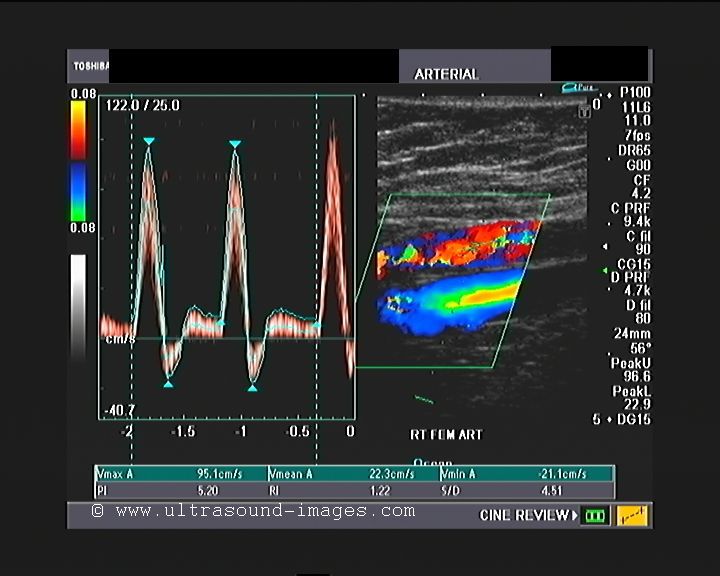

This elderly lady with a history of diabetes has evidence of ischemic changes of the right leg, with onset of gangrene of the toes. Colour Doppler study of the lower limb shows a severe stenosis of the right femoral artery, in its upper third. The diameter of the stenotic segment measured only 1.8 mm.

The prestenotic segment (Rt SFA/ femoral A) shows typical changes- steep upward slope of systole and shouldering of downward slope of systole (see green arrows in femoral A image).

Colour Doppler and spectral Doppler ultrasound examination of the stenotic segment of the right femoral artery shows a peak systolic velocity more than 190 cm/s (Vs). The peak systolic velocity in the pre-stenotic segment was 97 cm/s (Vp). The ratio Vs/Vp is greater than 2 suggesting a moderate to severe stenosis of the affected segment of the femoral artery.

The arterial tree below the femoral including the right popliteal, the right peroneal, posterior tibial and anterior tibial arteries all show moderate dampening off the blood flow in these arteries.